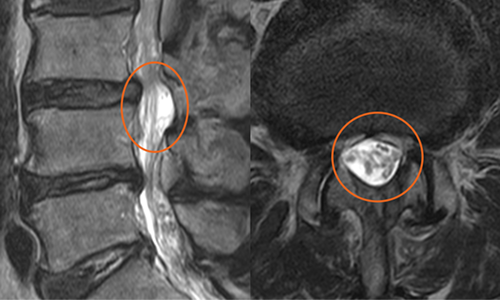

환자 : 79세 남성 증세 : 제 3,4번 요추간 비후된 황색 인대

경과 : 비후된 황색 인대가 제거된 결과, 비정상적인 신경의 신호가 하얗게 호전되고 신경근도 선명하게 드러남